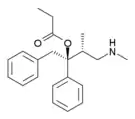

The first fully synthetic opioid was meperidine (later demerol), found serendipitously by German chemist Otto Eisleb (or Eislib) at IG Farben in 1932.[228] Meperidine was the first opiate to have a structure unrelated to morphine, but with opiate-like properties.[199] Its analgesic effects were discovered by Otto Schaumann in 1939.[228] Gustav Ehrhart and Max Bockmühl, also at IG Farben, built on the work of Eisleb and Schaumann. They developed "Hoechst 10820" (later methadone) around 1937.[230] In 1959 the Belgian physician Paul Janssen developed fentanyl, a synthetic drug with 30 to 50 times the potency of heroin.[211][231] Nearly 150 synthetic opioids are now known.[228]

- Fully synthetic opioids: such as fentanyl, pethidine, levorphanol, methadone, tramadol, tapentadol, and dextropropoxyphene;